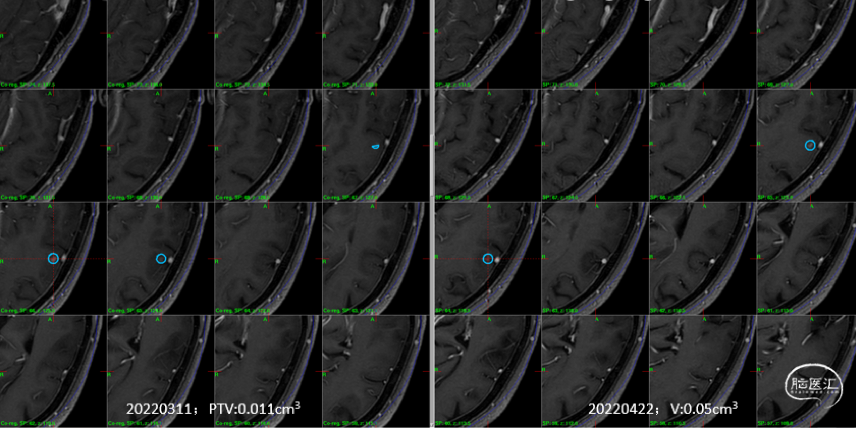

制定立体定向伽玛刀治疗计划(术中薄扫核磁扫面共发现4个病灶,除术前的2个病灶外,还发现2个小病灶);

影像随访:

6个月随访时,薄扫增强磁共振(1mm/层)提示肿瘤明显缩小,无放射相关不良反应,没有新发病灶;患者目前仍在规律的随访当中,期待我们的长期随访结果。